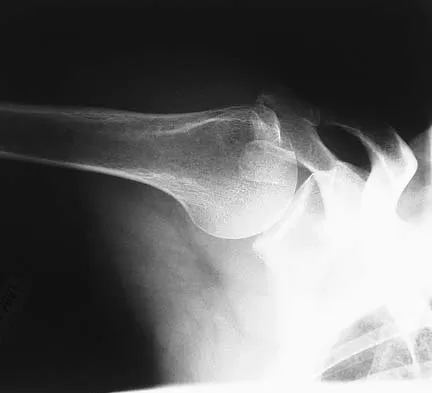

A 45-year-old man is seeking evaluation of an injury sustained in a motor vehicle accident 10 weeks ago. Current radiographs are shown in Figures 2a and 2b. Based on the radiographic findings, what is the most likely diagnosis?

An increased density of the talar body compared to the distal tibia following fracture of the talar neck is highly suggestive of vascular compromise of the talar body. Subchondral osteopenia of the talus at 6 to 8 weeks (Hawkins sign) is a favorable sign but does not eliminate the possibility of osteonecrosis. Elgafy H, Ebraheim NA, Tile M, Stephen D, Kase J: Fractures of the talus: Experience of two level 1 trauma centers. Foot Ankle Int 2000;21:1023-1029.